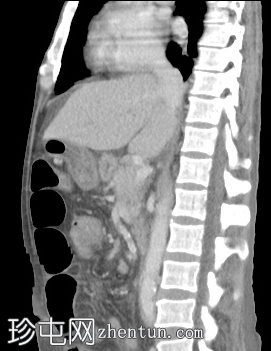

轴位增强扫描

动脉期

肝脏轻度肿大,未见肝内胆管扩张。近端和中段胆总管扩张至8 mm,远端突然中断,门周脂肪间隙增厚。

胰腺轻度肿大,胰周脂肪间隙增厚,符合急性胰腺炎表现。

胃大弯壁内可见一囊肿,大小为7.6 × 4.3 cm,囊壁厚度为2.5 mm,可见强化。脾门处可见另一囊肿,大小为 4.8 × 3.0 cm。

盲肠和升结肠壁水肿增厚,可能为反应性改变。

腹主动脉、脾动脉、腹腔干和肠系膜上动脉可见动脉粥样硬化改变。

中度腹水。双侧轻度胸腔积液(右侧较左侧多)。